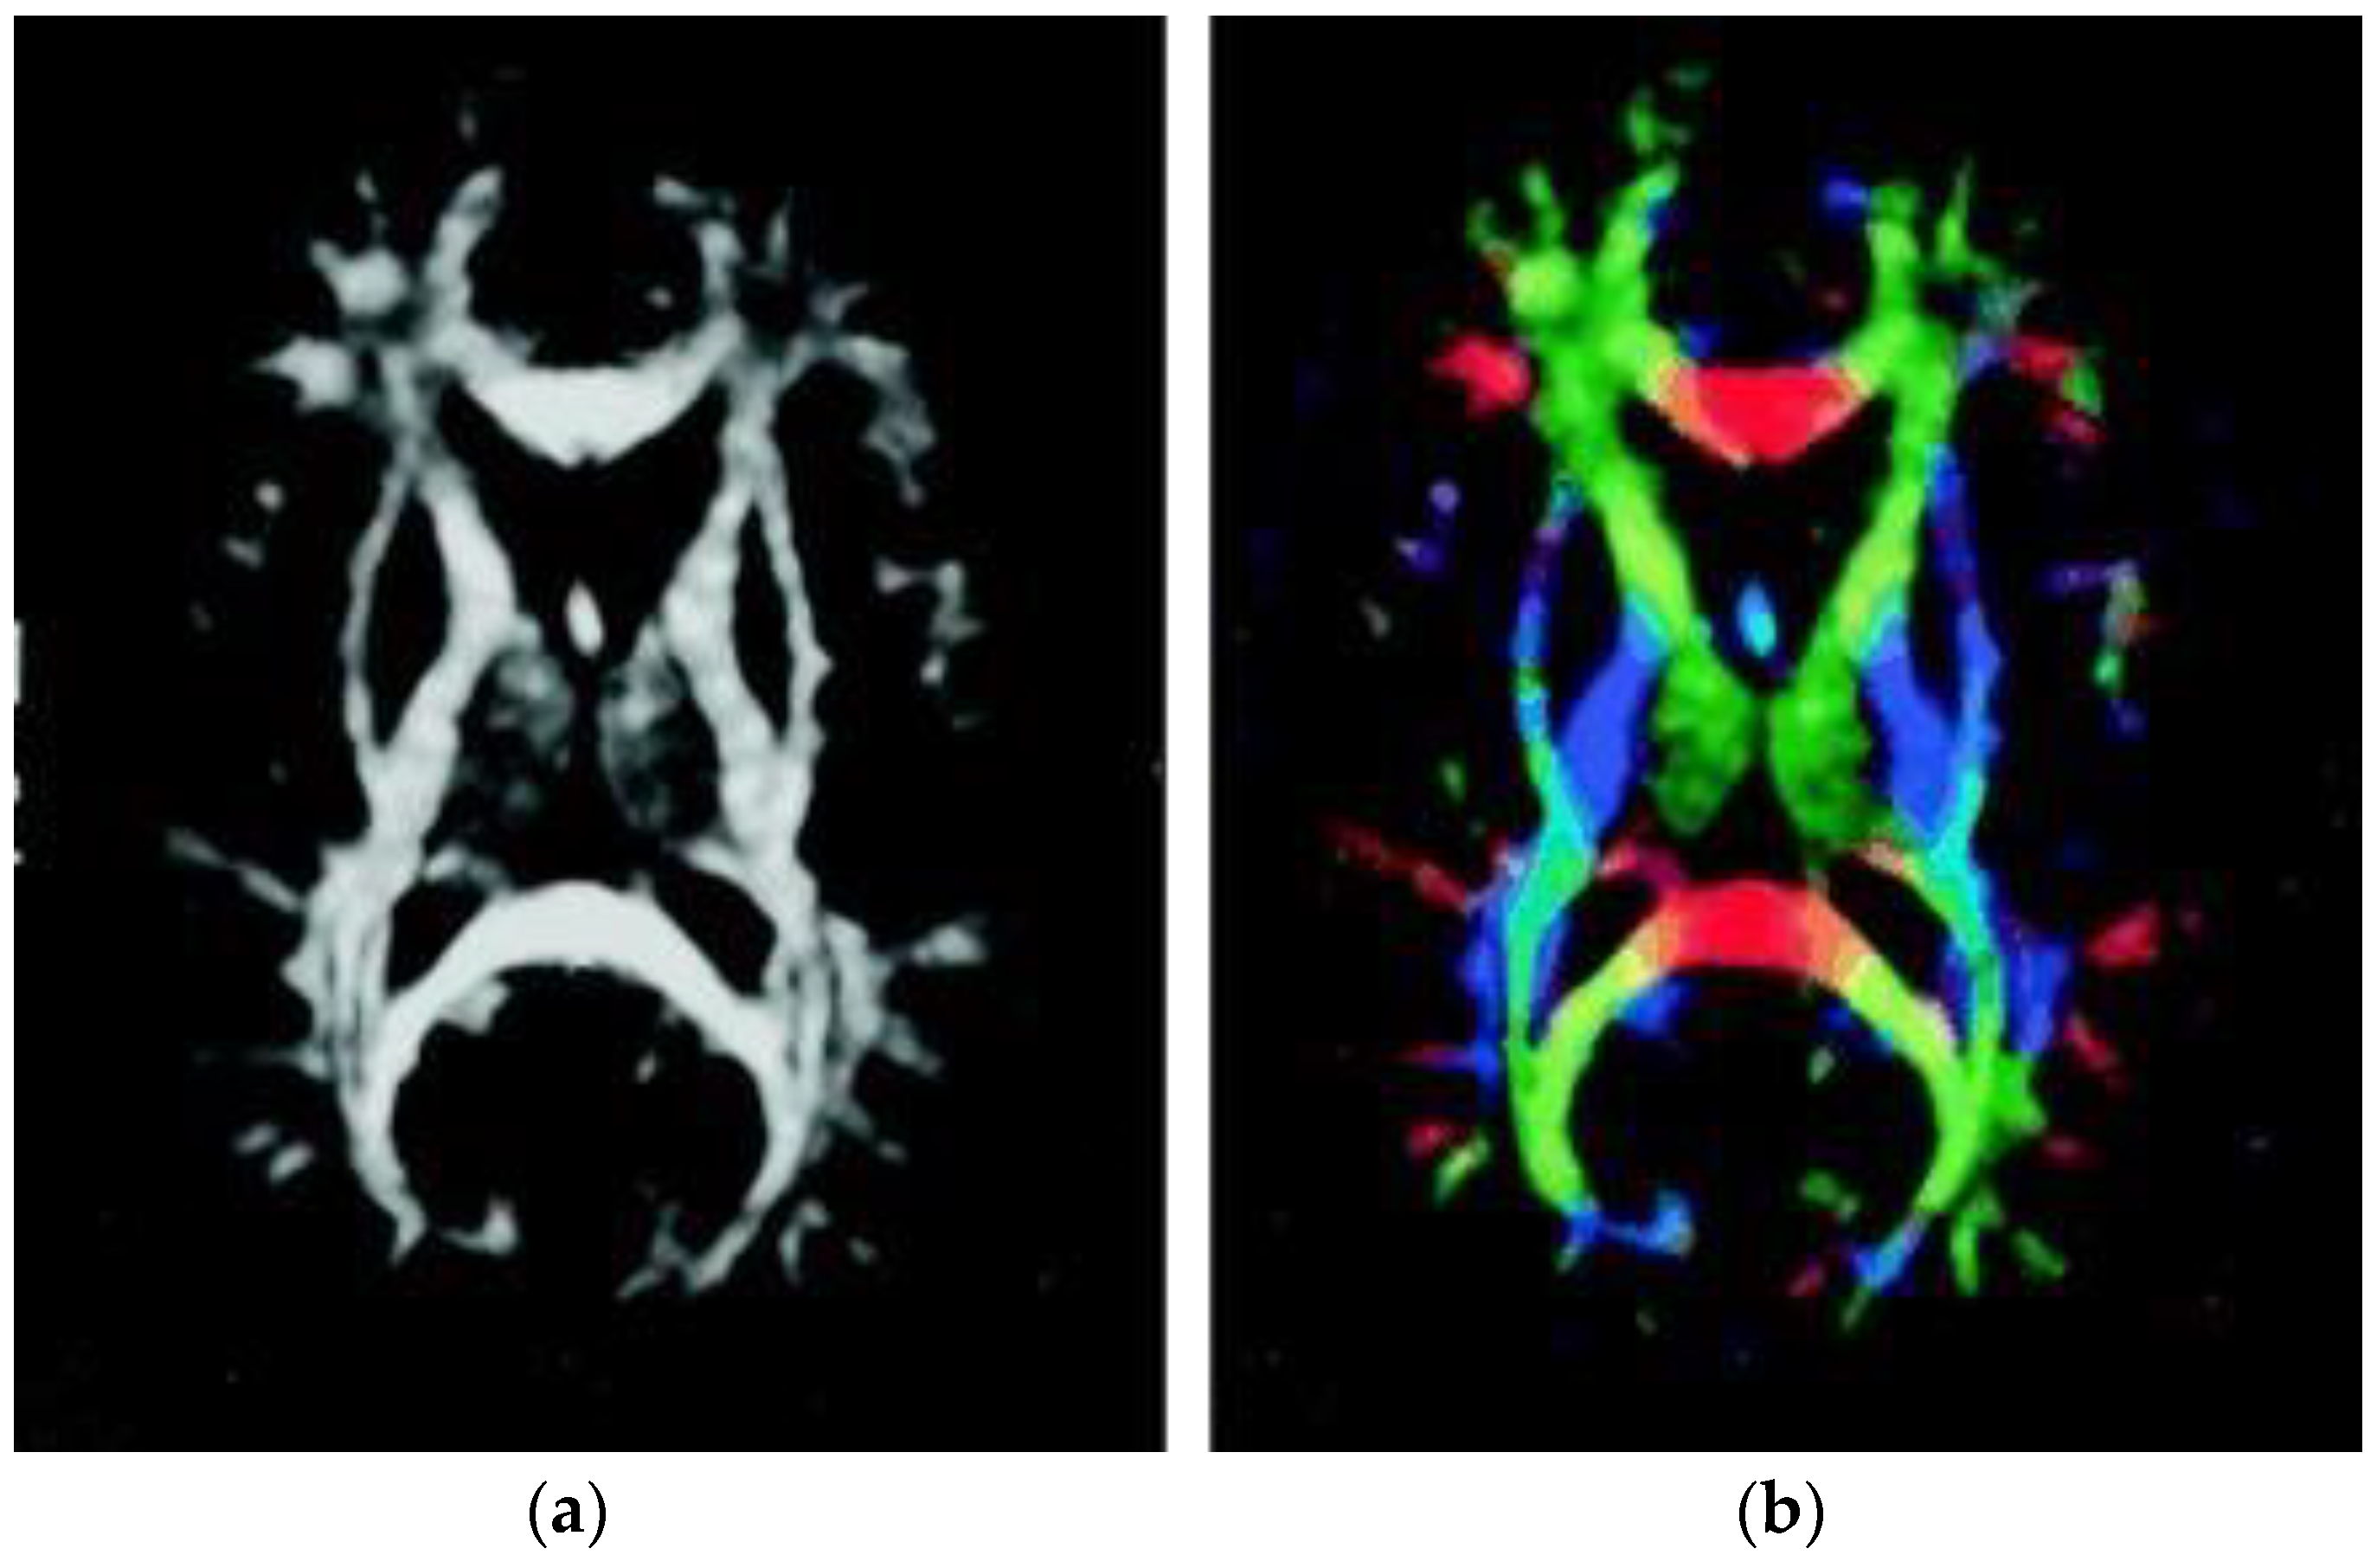

Diffusion tensor